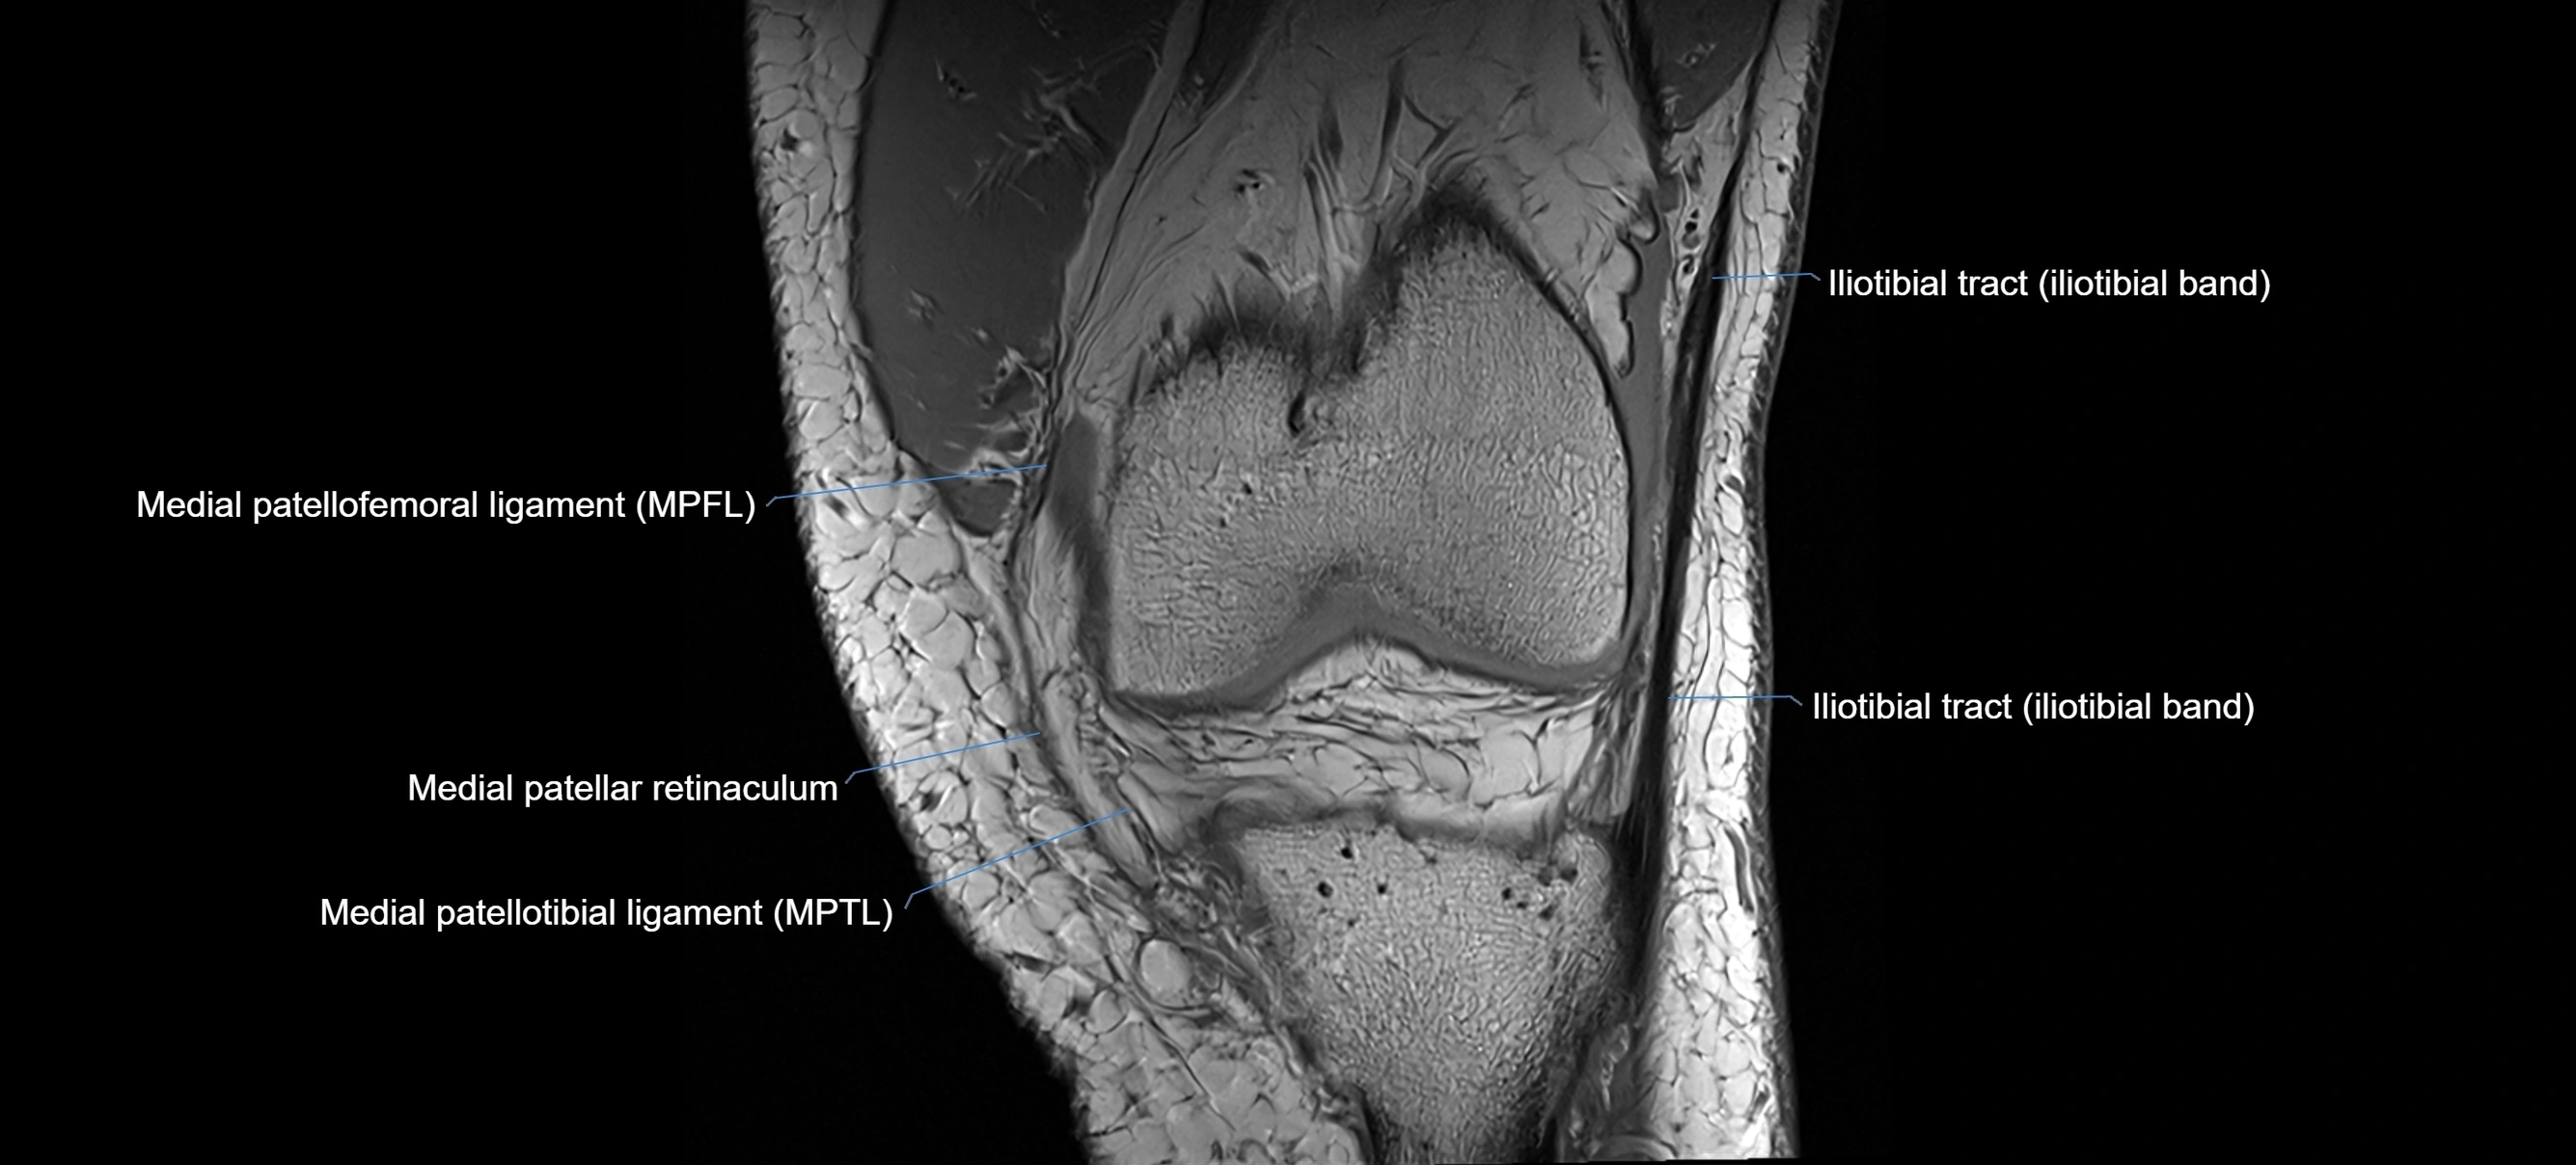

MRI Appearance

T1-weighted images:

• Normal ACL appears as a low-signal band-like structure crossing the intercondylar notch

• Surrounded by intermediate signal synovial fluid and fat planes

T2-weighted images:

• Normal ACL remains low signal

• Partial or complete tears appear as discontinuity, increased signal, or fiber laxity

MRI images

image